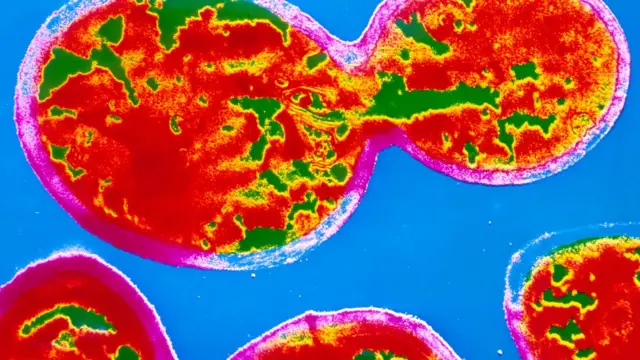

A mediados de los años 50, el científico belga Christian de Duve descubrió los lisosomas.

Se trata de unos orgánulos celulares capaces de "digerir" grandes cantidades de proteínas, carbohidratos, lípidos, e incluso otros orgánulos celulares, según explicó el Instituto Karolinska, encargado de entregar el Nobel de Medicina.

Estos corpúsculos también se dedican a reciclar los desechos de las células para convertirlos en material útil.